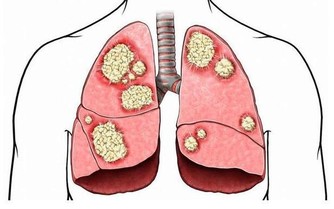

現代醫學界發現,免疫力與衰老有密切關係,免疫力減退是導致衰老的因素之一。並且,醫學界還越來越傾向於,提高免疫力能夠抑制腫瘤發生,預防腫瘤復發和轉移,對於癌症患者有重大意義。

而免疫系統,是人體自身的防禦機制,它最大的作用在於識別和消滅外來入侵的異物(包括病毒、細菌等),同時處理衰老、損傷等自身細胞(包括受感染或癌變的細胞),從而保護人們遠離疾病,讓人們保持年輕。

經常咳嗽,容易出現支氣管炎、咽喉炎、肺炎等炎症;如果是本身有哮喘的人,哮喘也會反復發作。

免疫力低下,容易生病怎麼辦? 不妨做4件事,提升免疫力